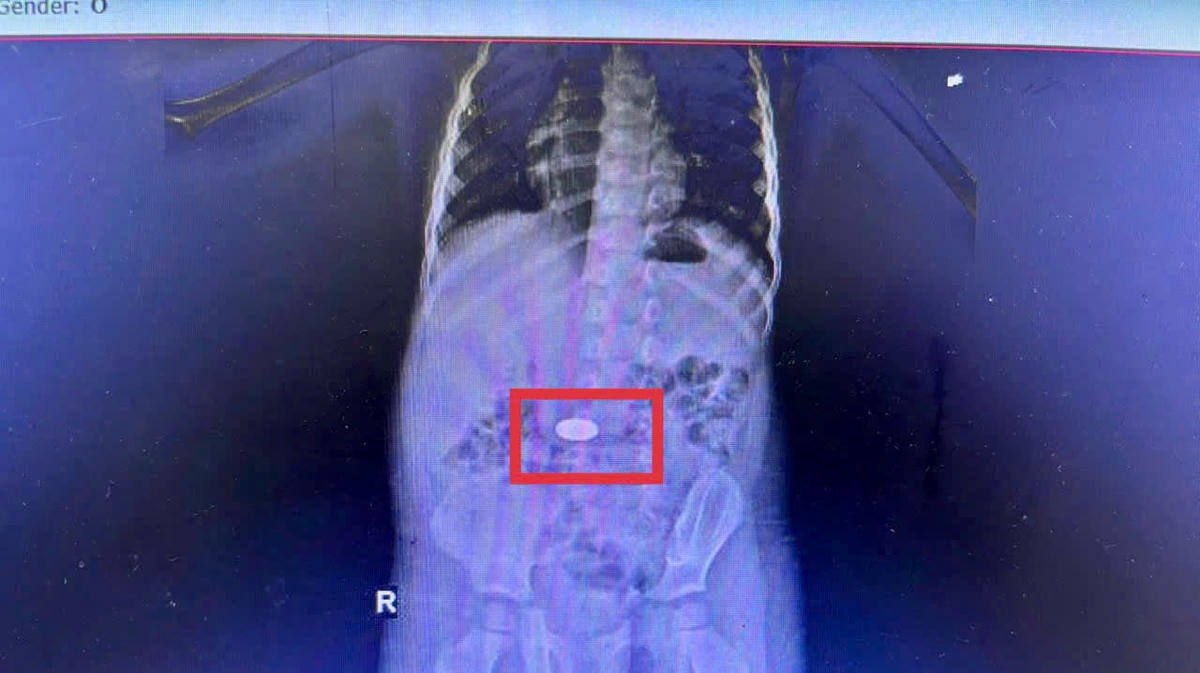

Tại Bệnh viện Sản Nhi Phú Thọ (tỉnh Phú Thọ), các bác sĩ vừa gắp thành công dị vật là pin cúc áo (một loại pin nhỏ) mắc kẹt trong thực quản bé trai 2 tuổi. Theo thông tin từ gia đình, trẻ đang chơi đùa thì bất ngờ nuốt phải, ho sặc sụa, tím tái, quấy khóc và khó thở. Nhận thấy nguy kịch, gia đình đưa con đi cấp cứu ngay. Tại bệnh viện, chụp X-quang phát hiện dị vật kim loại tại thực quản, nghi là khay pin cúc áo. Rất may, ê kíp bác sĩ Khoa Chẩn đoán hình ảnh nhanh chóng nội soi cấp cứu, lấy dị vật ra ngoài an toàn. Cháu nhỏ đã an toàn, nhưng nỗi lo về hóc dị vật đường thở vẫn còn nguyên. Chia sẻ vấn đề này, BSCKI Bế Thị Minh Quỳnh, Khoa Chẩn đoán hình ảnh, Bệnh viện Sản Nhi tỉnh Phú Thọ cho biết: Pin cúc áo dù còn trong khay vẫn tạo dòng điện và phản ứng hóa học sinh kiềm mạnh, gây bỏng niêm mạc thực quản rất nhanh. Đối với trường hợp này, em bé may mắn được đưa viện sớm, loại trừ các biến chứng. Với trẻ nhỏ, niêm mạc mỏng manh, nguy cơ loét thủng thực quản, viêm trung thất, nhiễm trùng nặng dẫn đến tử vong rất cao nếu chậm trễ.